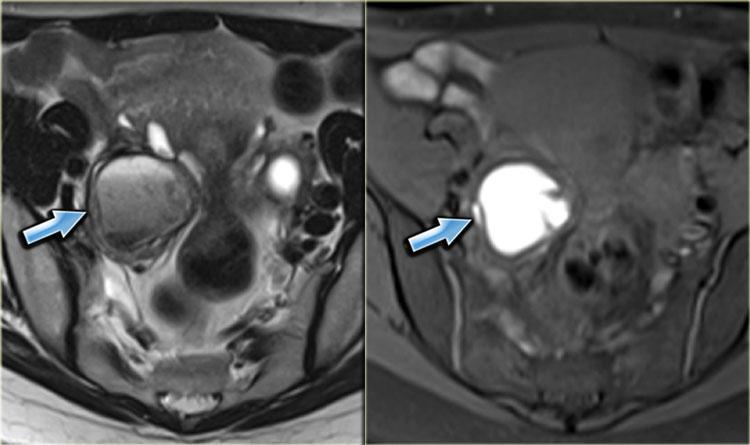

Bên trái là hình ảnh MRI của bệnh nhân bị lạc nội mạc tử cung thành bụng.

Trên chuỗi xung T2W, các tổn thương có tín hiệu đồng tín hiệu so với cơ, kèm theo các ổ nhỏ tăng tín hiệu, phản ánh các tuyến nội mạc tử cung bị giãn.

Trên ảnh T1W có xóa mỡ, các tổn thương có tín hiệu cao hơn một chút so với cơ (mũi tên).

Hình ảnh chuỗi xung T2W mặt cắt ngang bên trái minh họa một trường hợp lạc nội mạc tử cung thành bụng khác.